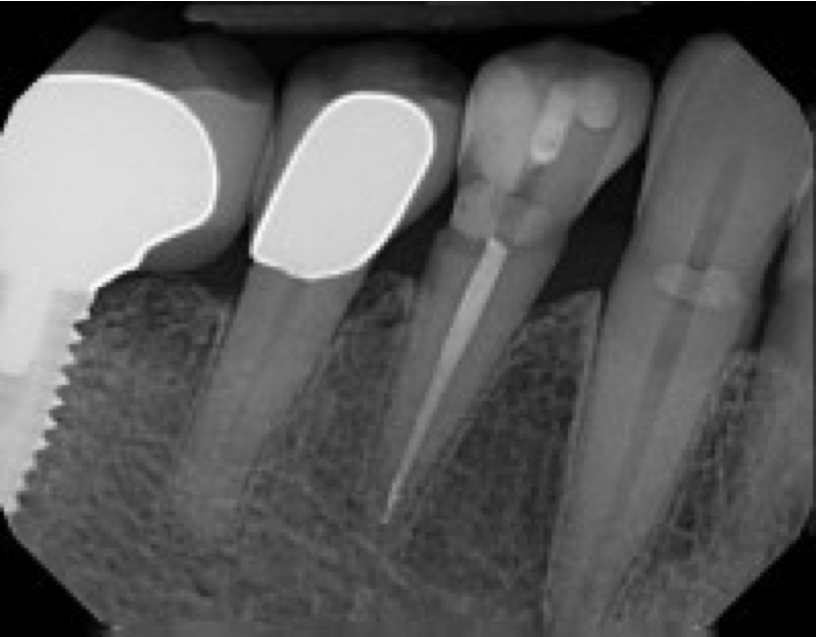

A 71-year-old man presented with acute pain in tooth No. 29 that was spontaneous, unresponsive to vitality testing, and sensitive to percussion. He was referred to an endodontist for treatment of acute apical periodontitis due to the non-vitality of the nerve. Because of the multiple restorations and lingual decay of the tooth, enamel and dentin were compromised, causing the tooth to be biomechanically at high risk and requiring an eventual post-and-core and crown (Figure 1 and Figure 2). Endodontic care included nonsurgical intracanal therapy and creating room for a post space.

Fig 1. Multiple restorations decrease enamel and dentin strength, requiring full-coverage enhancement.

Figure 1

Fig 2. Preoperative view of tooth to be restored shows defective Class 5 restoration that unfortunately was mirrored on the lingual gingival margin.

Figure 2